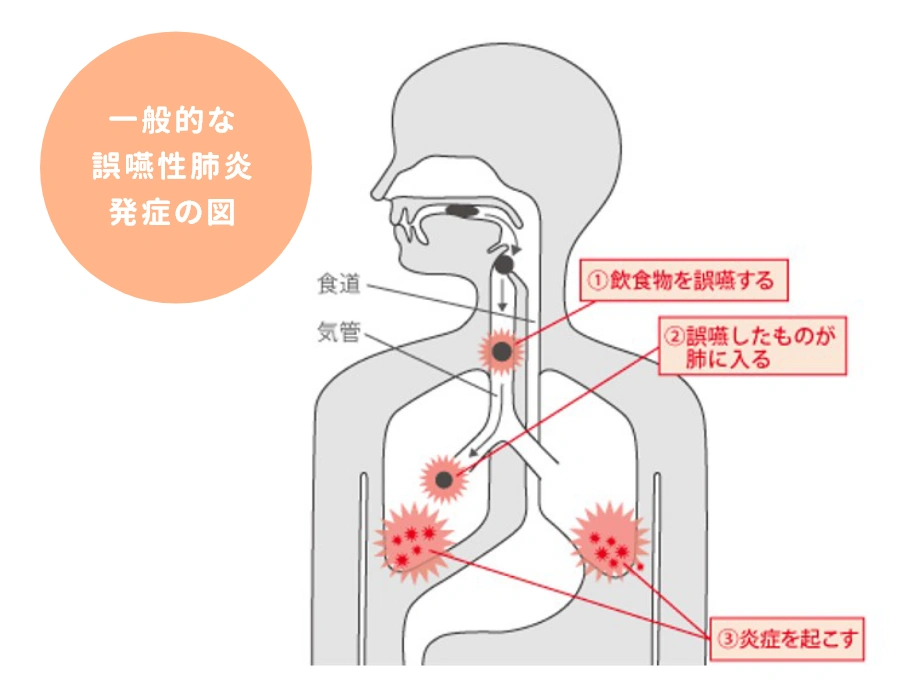

摂食嚥下障害とは、口から食べる機能の障害のことです。私たちは普段意識していませんが、食べ物を目や脳において認識して口まで運び、口の中に入れて噛み、ゴックンと飲み込むことで、食物から液体を摂取しています。これらの動作の1つまたは複数が、何らかの原因で正常に機能しなくなった状態を言います。 健康な成人の方であれば、誤って気管に入った場合も自然反射的に吐き出したり、細菌から身を守る免疫力が十分に備わっているので、大きな問題にはなりませんが、高齢者、 特に寝たきりや身体が不自由な方は、そうした自然反射的な動作が難しいので、細菌が気管に入りやすく、さらに抵抗力や免疫力の低下から、誤嚥性肺炎になりやすいと言われています。

摂食嚥下障害とは、どのような障害か

摂食嚥下障害とは、口から食べる機能の障害のことです。私たちは普段意識していませんが、食べ物を目や脳において認識して口まで運び、口の中に入れて噛み、ゴックンと飲み込むことで、食物から液体を摂取しています。これらの動作の1つまたは複数が、何らかの原因で正常に機能しなくなった状態を言います。 健康な成人の方であれば、誤って気管に入った場合も自然反射的に吐き出したり、細菌から身を守る免疫力が十分に備わっているので、大きな問題にはなりませんが、高齢者、 特に寝たきりや身体が不自由な方は、そうした自然反射的な動作が難しいので、細菌が気管に入りやすく、さらに抵抗力や免疫力の低下から、誤嚥性肺炎になりやすいと言われています。

2.誤嚥性肺炎

摂食嚥下障害とは、口から食べる機能の障害のことです。私たちは普段意識していませんが、食べ物を目や脳において認識して口まで運び、口の中に入れて噛み、ゴックンと飲み込むことで、食物から液体を摂取しています。これらの動作の1つまたは複数が、何らかの原因で正常に機能しなくなった状態を言います。 健康な成人の方であれば、誤って気管に入った場合も自然反射的に吐き出したり、細菌から身を守る免疫力が十分に備わっているので、大きな問題にはなりませんが、高齢者、 特に寝たきりや身体が不自由な方は、そうした自然反射的な動作が難しいので、細菌が気管に入りやすく、さらに抵抗力や免疫力の低下から、誤嚥性肺炎になりやすいと言われています。